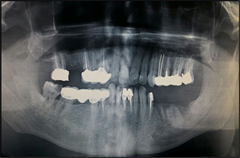

2.3. Radiographic Examination

Dental panoramic radiographs were used for radiographic examination as an overview of the affected structures. Measurements of the distance between cemento-enamel junction (CEJ) and bone level (BL), was done with a calliper to the nearest 0.1 mm.

If one or more of these landmarks could not be determined or caries had destroyed the cemento-enamel junction the tooth was excluded from the study (Figure 3 and Figure 4).

Figure 3. Radiographic of evaluation of patient with amalgam filling class.

Figure 4. Radiographic evaluation of patient with fixed partial denture.